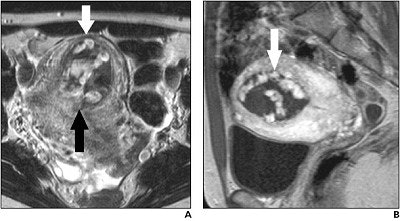

| This 32-year-old woman presented with vaginal bleeding and a serum b -human chorionic gonadotropin level of 45 mlU/mL, two weeks after a spontaneous abortion. An axial T2-weighted image (A) showed an irregular uterine mass (black arrow) of heterogenous intensity. The white arrow points to marked thinning of the myometrium. Image B is from the same patient, a sagittal T1-weighted contrast-enhanced scan that shows areas of brisk enhancement (arrow) in intrauterine mass. Noonan JB, Coakley FV, Qayyum A, Yeh BM, Wu L, Chen L. "MR Imaging of Retained Products of Conception," (AJR, Vol. 181, pp. 435-439). |

"Our results suggest that retained products of conception appear on MR imaging as an intracavitary uterine soft-tissue mass with variable T1 and T2 signal intensities, variable amounts of enhancing tissue, and variable degrees of myometrial thinning and obliteration of the junctional zone," they wrote.

In comparison, previous descriptions of placental-site trophoblastic tumor on MR have suggested that the tumor is intramyometrial in location, rather than intracavitary, they explained.